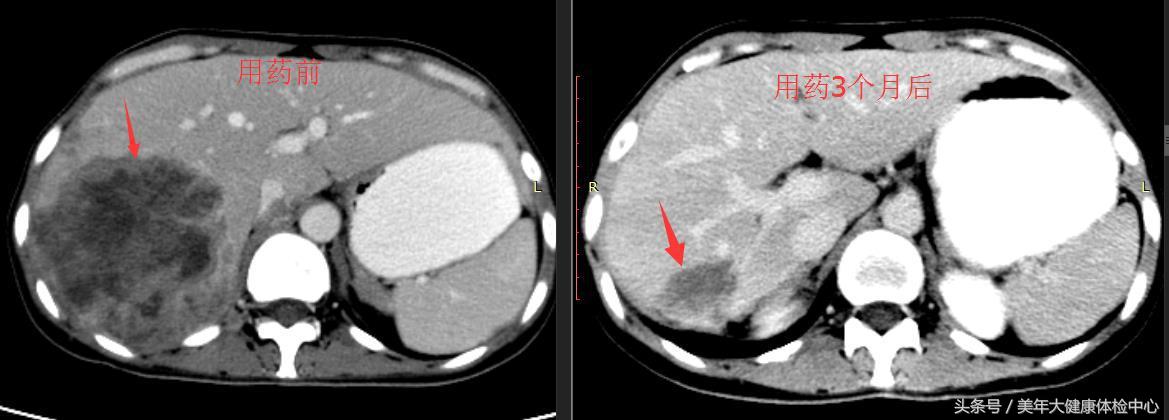

2014年12月25日和2016年1月16日之间,对426名患者进行筛选,其中188名有ctDNA EGFR突变的患者被纳入,并接受吉非替尼治疗。183名患者进行了一次或多次基线后肿瘤评估,被纳入主要疗效分析。中位随访时间为14.5个月(IQR 12.2-16.5)。在数据截止时(2017年1月31日),152名患者疾病进展或已死亡。达到客观反应的比例为72.1%(95%CI 65.0-78.5)。中位无进展生存期为9.5个月(95%CI 9.07-11.04)。在167名有可用血样的患者中,147名(88%)在第8周时ctDNA 中的EGFR突变清除,这些患者的中位无进展生存期比20名第8周时EGFR突变持续的患者更长(11.0个月[95%CI 9.43-12.85] vs 2.1个月[1.81-3.65];风险比[HR] 0.14,95 %CI 0.08-0.23;p<0.0001)。根据179名患者的基线NGS数据,研究确定了3个亚组患者:只有EGFR突变的患者(n=58)、EGFR和肿瘤抑制基因突变的患者(n=97)、以及EGFR和癌基因突变的患者(n=24)。这些亚组的中位无进展生存期分别为13.2个月(95%CI 11.5-15.0),9.3个月(7.6-11.0)和4.7个月(1.9-9.3)(只有EGFR突变 vs EGFR和肿瘤抑制基因突变,HR 1.78,95%CI 1.23-2.58;p=0.002;只有EGFR突变 vs EGFR和癌基因突变,2.66,1.58-4.49;p=0.0003)。最常见的3级或4级不良事件是肝功能异常(n=24)。17名(9%)患者报告了严重不良事件。没有发现吉非替尼的意外安全事件。

检测ctDNA中的EGFR突变是识别一线吉非替尼治疗受益患者的有效方法。进一步分析EGFR突变的动态改变和伴随的基因畸变可以预测吉非替尼耐药性。